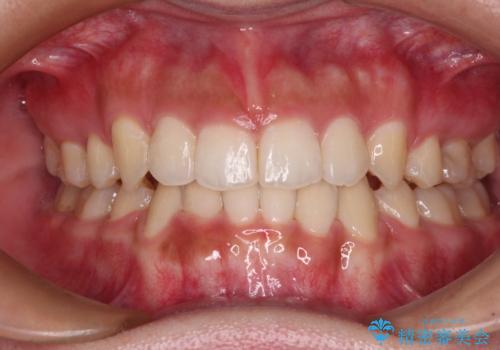

著しい八重歯が気になる インビザラインでの矯正治療

- 顕著な八重歯が気になるとのことで来院された患者様です。

インビザラインでの治療を希望されましたが、インビザライン単独では困難と判断されたため、補助装置や一部ワイヤー装置を用いて行うこととしました。

叢生が強いため、上下左右第一小臼歯4本を抜歯することとしました。